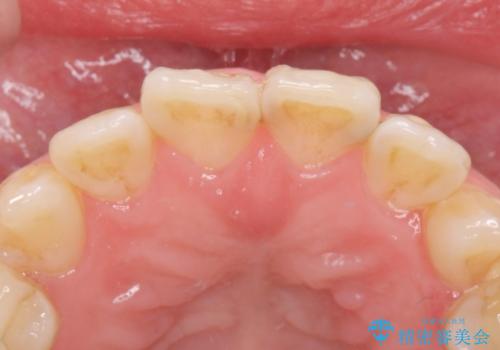

前歯綺麗にしたい。

- 前歯を綺麗にしたいとの事で来院。

まずは仮歯を発注して仮歯にして最終的な被せ物の形を整えてジルコニアクラウンstで処置を行いました。